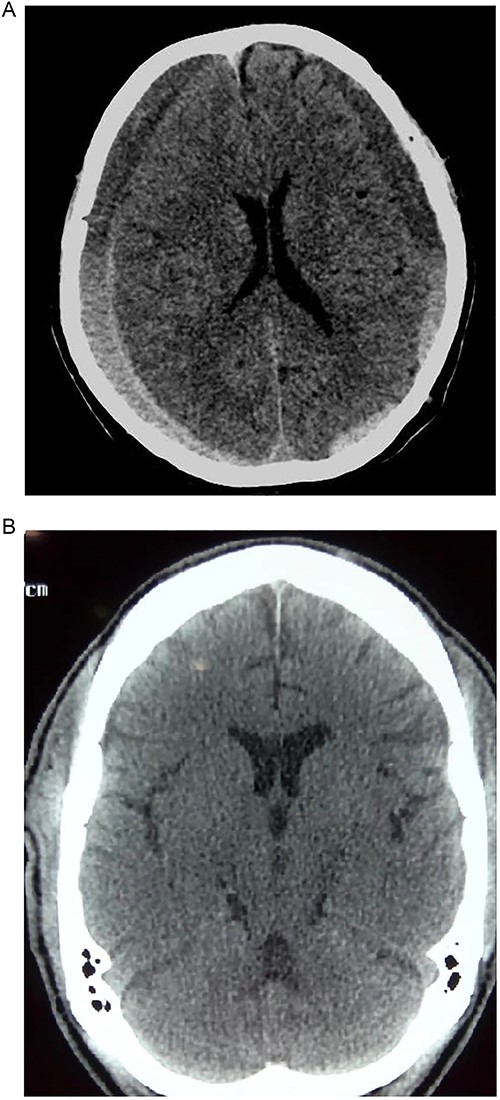

Case 3 – left isolated foot drop

A 78-year-old man with a 1-week history of headaches and dragging of the left foot. He had fallen in the bathroom 6 weeks prior to presentation. He had no other symptoms. Examination was unremarkable except for a left-sided foot drop with increased ankle jerk reflex. Brain CT done revealed a right-sided fronto-parieto-temporal CSDH (Figs 3 and 4). He had burr hole drainage and was discharged 3 days later to continue physiotherapy at home. At 4 weeks follow-up, his symptoms had completely resolved.

While few reports of bilateral lower extremity weakness have been reported with CSDH, unilateral foot drop is extremely rare. Two previous cases of isolated foot drop from CSDH have been reported, Sengupta et al. [17] and Weisberg [18]. Direct cortical compression of the motor foot area of the homunculus against the falx cerebri is the likely explanation in this scenario given the large right hemispheric CSDH. While the clinical suspicion of an intracranial lesion was considered due to raised ankle reflex, a diagnosis of CSDH before imaging was not entertained because of the rarity of isolated foot weakness.